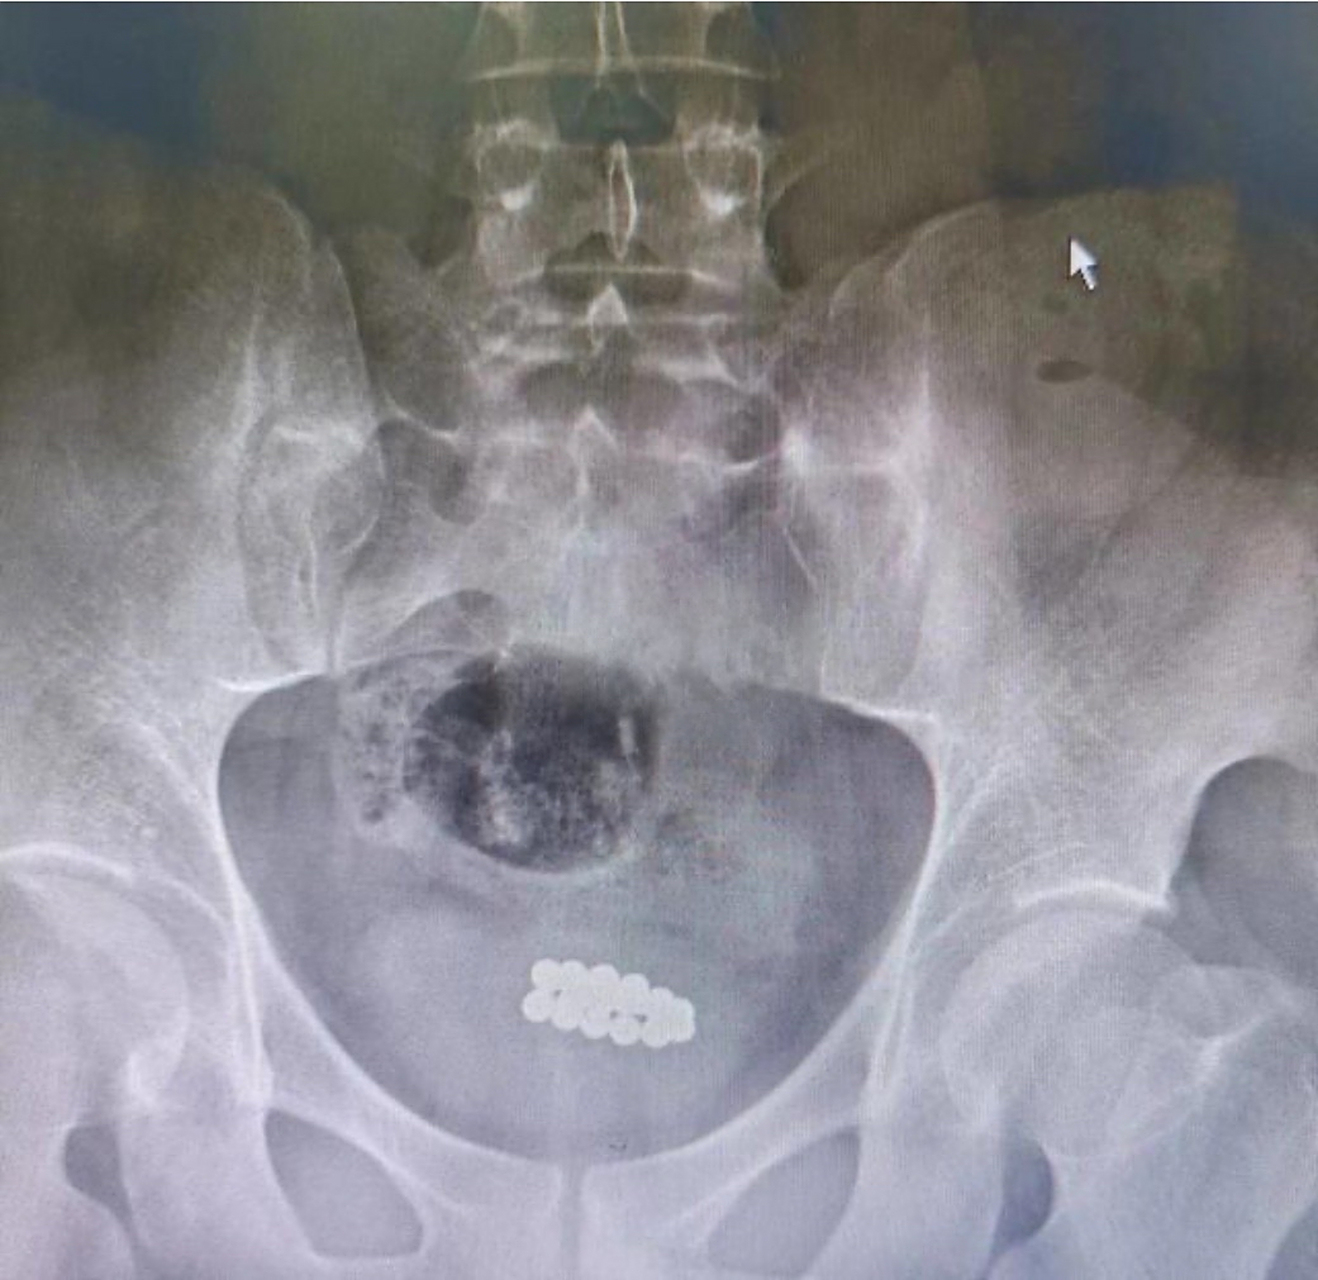

这名男子将磁力珠一颗一颗的塞进自己的尿道,一共是塞了29颗而且我看了一下视频中每一个磁力珠的直径还是非常大的因为这29颗磁力珠都是相互吸引的,所以塞进去以后就会相互连在一起然后这名男子把这个磁力珠塞进去,已经有几周的时间了,而且在这几周的时间里,这些磁力柱逐渐向深处移动,最终;起初大家只是觉得音乐声音有点大,但是看到健健开心的样子就没有多说什么就这样过了一个星期,健健和爷爷说自己头疼,耳朵疼大家赶紧带健健去医院,医生给健健测了听力,发现健健的听力出现了严重下降医生指出声音过大的电音吉他正是导致宝宝出现听力下降的罪魁祸首,幸亏来得及时,不然听力持续下降后。

尤其是年龄较小的时候,一定要注意孩子的安全,有些时候孩子在玩耍时很容易会被玩具或者是其他物品所伤害,程度较轻的话一定时间内就会痊愈,如果将宝宝伤害的伤口过大,很容易就会给宝宝产生后遗症等问题,这样子家长也会追悔莫及所以在孩子日常生活当中玩耍时,家长一定要注意有些物品千万不要让孩子;又称巴克球 而且 医生根据磁力珠在小杰体内的形态推测 孩子很有可能已经发生了 肠穿孔 于是通知家长 立刻给孩子进行急诊手术 手术中医生发现 11颗磁力珠分别位于3段不同的肠管 已经导致了 4处肠管穿孔 随后,医生们通过 腹部一个小切口将11颗磁力珠取出 然后再缝合修补穿孔的肠管 经过治疗和护理 目前。

1 巴克球磁力珠巴克球,是一种带有强磁性的金属实心小圆球在网上,商家大多标注“强磁百变益智”为卖点,价钱也不贵,100颗大概10多块,可谓“物美价廉”了但是,这种巴克球又小又滑,很容易被宝宝误吞,一旦误吞分分钟是要命的事情这种玩具不论孩子多喜欢都不要买给他,这种东西。